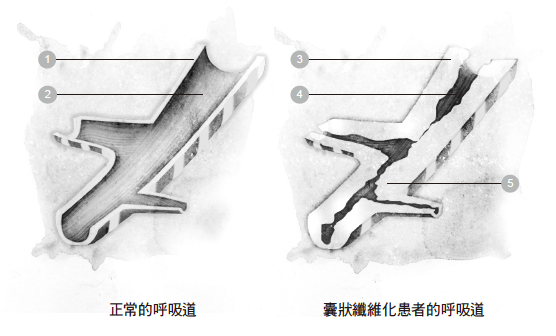

◆阻塞性肺病

阻塞性肺病的症状让患者很难吐出适量的空气,这类疾病的特点是长期呼吸不顺畅,而不顺畅的原因在于呼吸受到「阻碍」,并且阻碍的程度随着时间而日渐严重。就是这种阻碍,导致患者无法轻松自在地呼吸空气。这类肺病经常被称为「慢性阻塞性肺病」(chronic obstructive pulmonary disease, COPD,又称为chronic obstructive lung disease, COLD),或是「慢性阻塞性呼吸道疾病」(chronic obstructive airway disease, COAD)。

「慢性阻塞性肺病」的患者之所以呼吸短促,是因为他们无法充分把空气从肺部排出去。呼吸气流不顺畅的原因是肺脏受损,或是肺脏内的呼吸道太过狭窄,因而造成他们呼出气流的速度比正常人慢得多。这类患者做完吐气的动作之后,肺里面还留着异常大量的空气,于是他们很难再吸入空气。

「阻塞性肺病」会让呼吸成为一件苦差事,当患者的活动量或劳动量增加时,情况更是雪上加霜。简单地说,患者还来不及把所有空气吐出去,马上又必须吸入下一口空气了。在美国和欧洲国家,「阻塞性肺病」是常见死因的第三名,前两名是癌症和心脏病。这类疾病虽然可以治疗,但目前还没有完全根治的方法。

「阻塞性肺病」最常见的例子包括:

.气喘

.肺气肿

.慢性支气管炎

.支气管扩张

.囊状纤维化

❍慢性支气管炎

支气管炎是指支气管发炎了,而支气管是空气进入肺脏的通道。支气管炎会引发咳嗽、呼吸短促、喘息和胸口紧绷。它又可以分为两个类别:急性支气管炎和慢性支气管炎。

在慢性支气管炎患者的身上,支气管发炎的地方会产生大量黏液,结果是引发咳嗽,而且造成空气难以进出肺脏。

香烟是支气管炎最常见的病因,不光是抽烟者本人会受害,连被迫吸入二手烟的人也难逃其害。长时间吸入其他烟雾、灰尘的人,也可能罹患慢性支气管炎。尽管就医治疗有助于减缓症状,可是慢性支气管炎是一种长期性的疾病,会不断复发,几乎无法彻底痊愈。

❍支气管扩张

支气管扩张是另一种需要加以治疗的疾病,这种疾病是为了排除黏液而造成呼吸道受损。

当灰尘、细菌和其他微小的分子被吸入呼吸道时,黏液有助于清除这些东西,将它们排出呼吸道。不过,在支气管扩张患者的身上,他们的呼吸道逐渐丧失排除黏液的能力,于是黏液越积越多,成为细菌滋生的温床,使得肺部反复遭到感染。每感染一次,呼吸道就受损得更厉害;久而久之,空气要进出肺脏就越来越困难了。

❍囊状纤维化

囊状纤维化是一种遗传性疾病,问题出在产生黏液的腺体上。肺脏和鼻腔里面有成排的细胞负责制造黏液。在正常的情况下,黏液是滑腻的液态物质,作用是维持肺脏内膜的湿润,防止肺脏干掉或是遭到感染。不过,在囊状纤维化的患者身上,黏液变得又厚又黏,堆积在肺脏里面,结果空气无法顺利进出呼吸道。如同支气管扩张的病症一样,堆积的黏液成了细菌滋生的温床,一再导致肺脏受到严重的感染。时日一久,肺脏就严重受损。

1 呼吸道内壁 3 又厚又黏的黏液阻 5 细菌感染

塞了呼吸道

2 呼吸道内膜有薄薄 4 黏液内的血液

的一层黏液